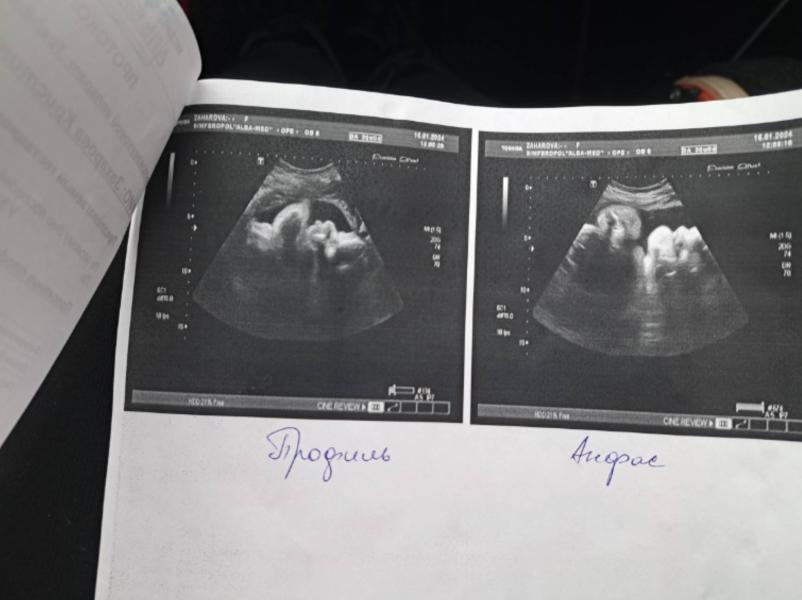

36 недель беременности: УЗИ, вес 2703, обвития нет, скоро роды?

Сегодня нам 36 полных недель, сходили на последний прием УЗИ, все отлично, вес уже 2,703,обвития нет, положение правильное, кислорода хватает)

Там такиииие щечки , прям пухляшка😍